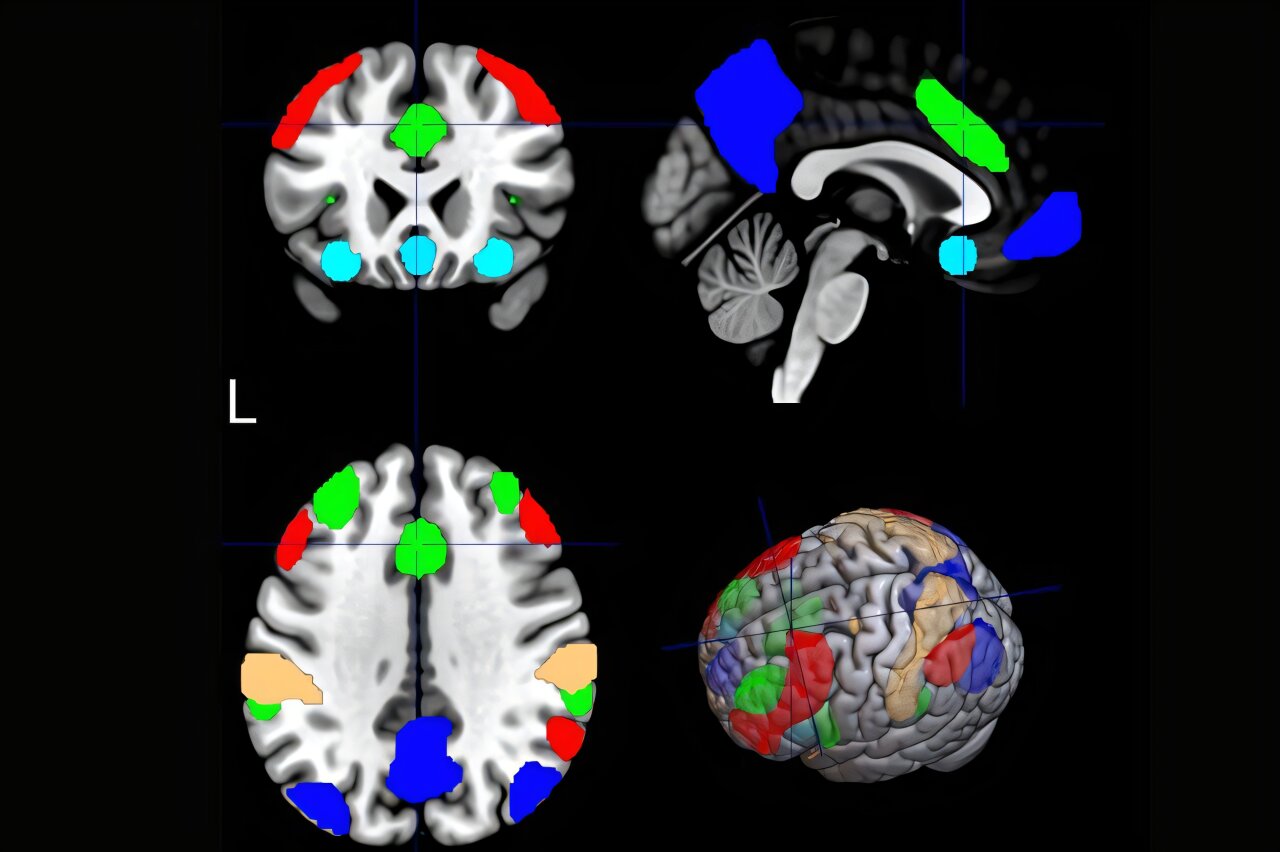

La nouvelle étude MUSC devient encore plus ciblée que cela, en utilisant une forme d’IA appelée apprentissage automatique pour analyser les images des réseaux de neurones du cerveau pour voir s’il est possible de prédire quels fumeurs sont susceptibles de bénéficier de plusieurs sessions de SMTR, également appelées TMS répétitives.

Pour ce faire, les chercheurs ont utilisé l’imagerie par résonance magnétique fonctionnelle, ou IRMf, pour détecter les changements dans le flux sanguin pour mesurer l’activité cérébrale. Ils ont regardé les réseaux de neurones lorsque les participants étaient dans un état de repos, détendus les yeux fermés et lorsqu’ils ont été exposés à des photos fumeurs.

Cette analyse a révélé qu’un réseau neuronal se démarquait: le réseau de saillance. Il filtre les informations pour déterminer ce qui est saillant ou important sur lequel se concentrer. Dans l’étude, la connectivité du réseau de saillance était le meilleur prédicteur de l’efficacité du SMTR.